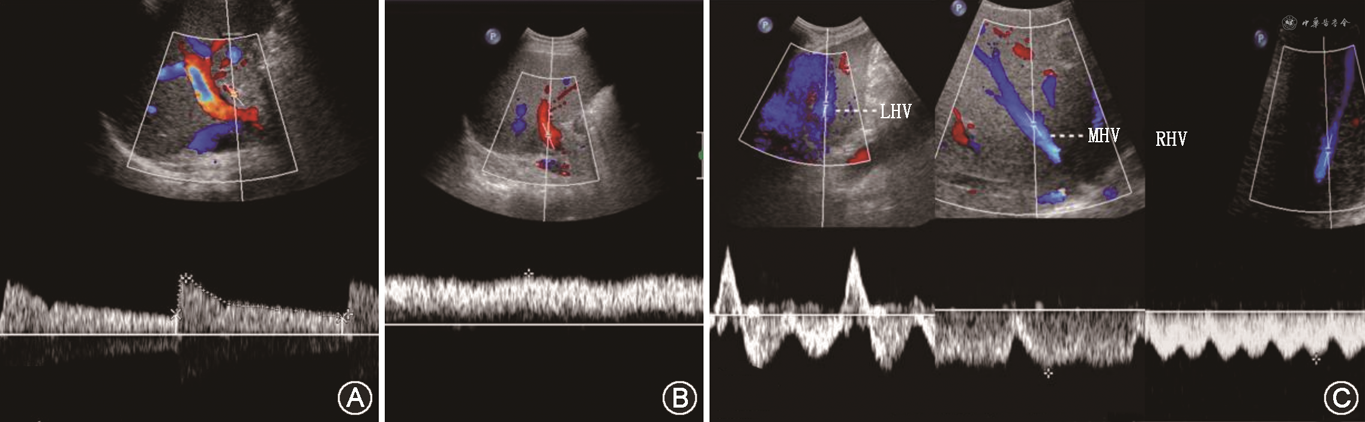

(2)HAS:HAS发生率为2%~11%,中位发生时间为移植后100 d[58],发生部位多见于肝动脉吻合口。与钳夹损伤、供受体肝动脉大小不匹配、肝动脉留置过长扭曲等手术技术因素有关。非吻合口部位肝动脉广泛性狭窄主要与移植肝排斥反应有关。CDFI检测到肝内动脉出现“tardus-parvus”频谱(RI<0.5及SAT>0.08 s),需考虑HAS可能[40]。此时应注意观察肝动脉吻合口处,尽可能直接显示HAS段,CDFI可见狭窄段局部呈“五彩镶嵌”花色血流,PSV>200 cm/s[59],或狭窄处PSV是其近端正常处测值的3倍以上[60](图12)。需注意,单独以肝内动脉出现“tardus-parvus”频谱诊断肝动脉吻合口狭窄假阳性率较高,达11.2%。以肝动脉“tardus-parvus”频谱与PSV降低(<48 cm/s)联合诊断HAS,假阳性率可降低为1%,特异度可从88.8%提高到99.1%[61]。超声造影可进一步改善肝动脉的显示,较CDFI更易直接观察到肝动脉吻合口狭窄段,可判断狭窄位置、程度及类型[62]。超声造影诊断HAS的灵敏度为92.3%,特异度为87.5%;与CDFI比较,超声造影可减少HAS的假阳性发现[63]。

(4)脾动脉窃血综合征(splenic artery steal syndrome,SASS):SASS是指扩张的脾动脉从肝动脉处窃取或抢夺了血流,使得肝动脉向肝实质内血流灌注减少的一种现象。SASS发生率为3.1%~5.9%,主要发生在具有脾功能亢进、脾动脉相对增宽的肝硬化患者。SASS多发生在移植术后2个月内,是急性HAT重要原因之一。SASS发生时,CDFI在肝内、外动脉测及低速高阻血流(PSV<35 cm/s,RI>0.8),同时可见脾肿大、脾动脉增宽[66]。超声造影表现为肝动脉延迟出现(肝动脉与门静脉造影剂出现的时间差缩短)、显影暗淡;同时可见门静脉显影明显增强[67, 68](图15)。需注意,超声造影发现肝动脉延迟出现且显影暗淡时,还需排除其他导致移植肝动脉低灌注的原因如肝动脉血管收缩、HAS等,联合应用超声造影及CDFI检查可进行鉴别,流程如图16所示[33,69]。